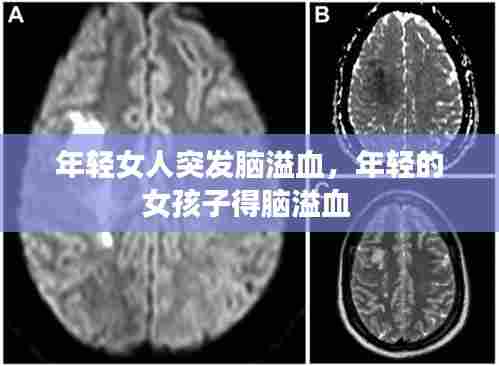

脑溢血是一种严重的脑部疾病,如果不及时治疗,可能导致生命危险。在医院里,医生迅速对李婷进行了CT检查,确诊为脑溢血。随后,她被紧急送往手术室,接受开颅手术。手术过程中,医生们争分夺秒,试图挽救李婷的生命。